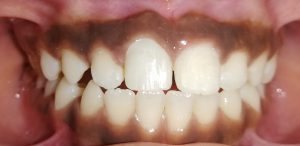

- Proposed a modification of Angle’s classification for application in primary dentition and various cross sectional studies have been carried out to validate its application.